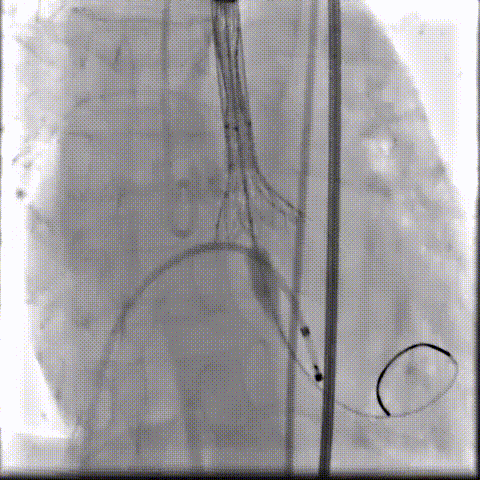

根部造影可见返流;20mm球囊预扩,LCA灌注缝隙狭小

预置LCA保护;第一次释放,

团状钙化挤压导致瓣膜(AV23)少量下滑

回收后重新定位,第二次释放,

瓣膜(AV23)深度仍未达到最佳预期

完全回收,第三次定位释放,瓣膜(AV23)位置良好

瓣膜工作位释放“烟囱支架”;

瓣膜(AV23)完全释放后,“烟囱支架”后扩

最终造影,“烟囱支架”显影清晰,瓣膜形态及LCA灌注良好